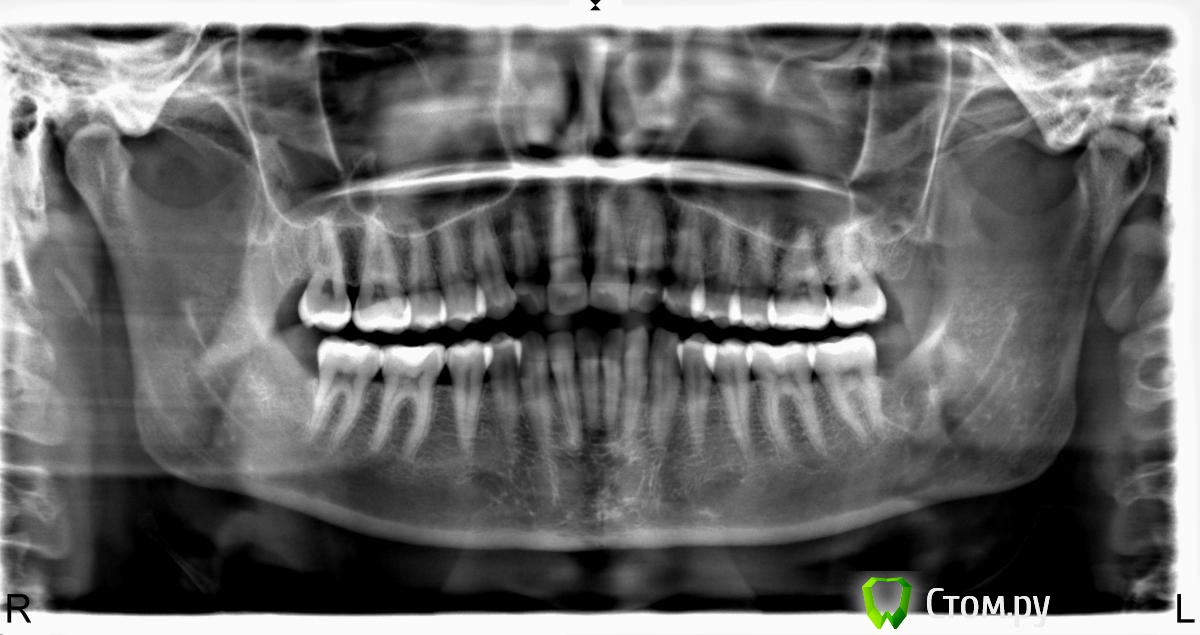

Алина-малина Опубликовано 25 января, 2014 Автор Поделиться Опубликовано 25 января, 2014 одной фотогафрией тут не хватит, попросите снимки у стоматологво у котрых были, либо сделайте новые http://forum.stom.ru...655-patcientam/)Добавляю снимок. Посмотрите пожалуйста((( Ссылка на комментарий